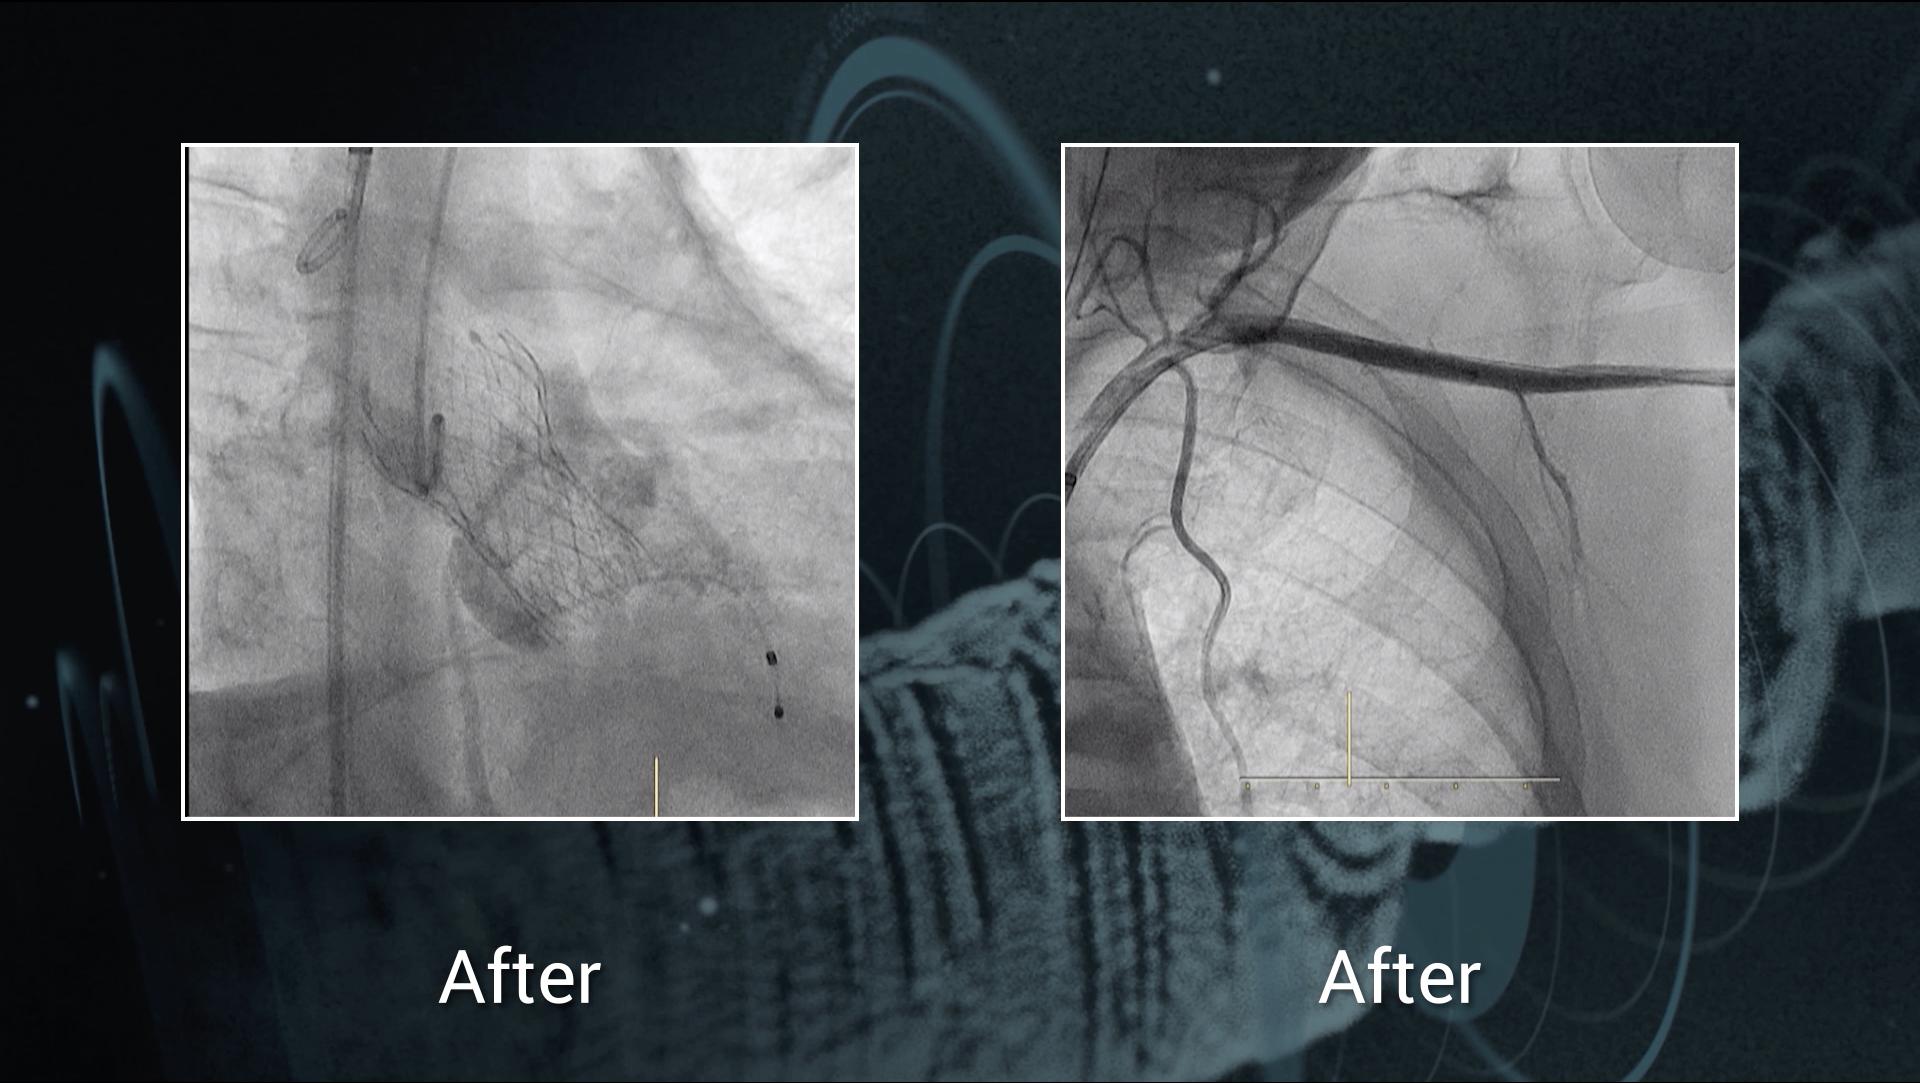

2 VRT - High risk coronary occlusion TAVI tips and tricks

Valve-in-Valve with high risk coronary occlusion & Microcirculation assessment in 202

Treatment of bicuspid severe aortic stenosis via percutaneous transaxillary TAVR

Dr Eric Van Belle, Dr Cédric Delhaye, Dr Flavien Vincent, Dr Tomas Modine & Dr Philippe Généreux